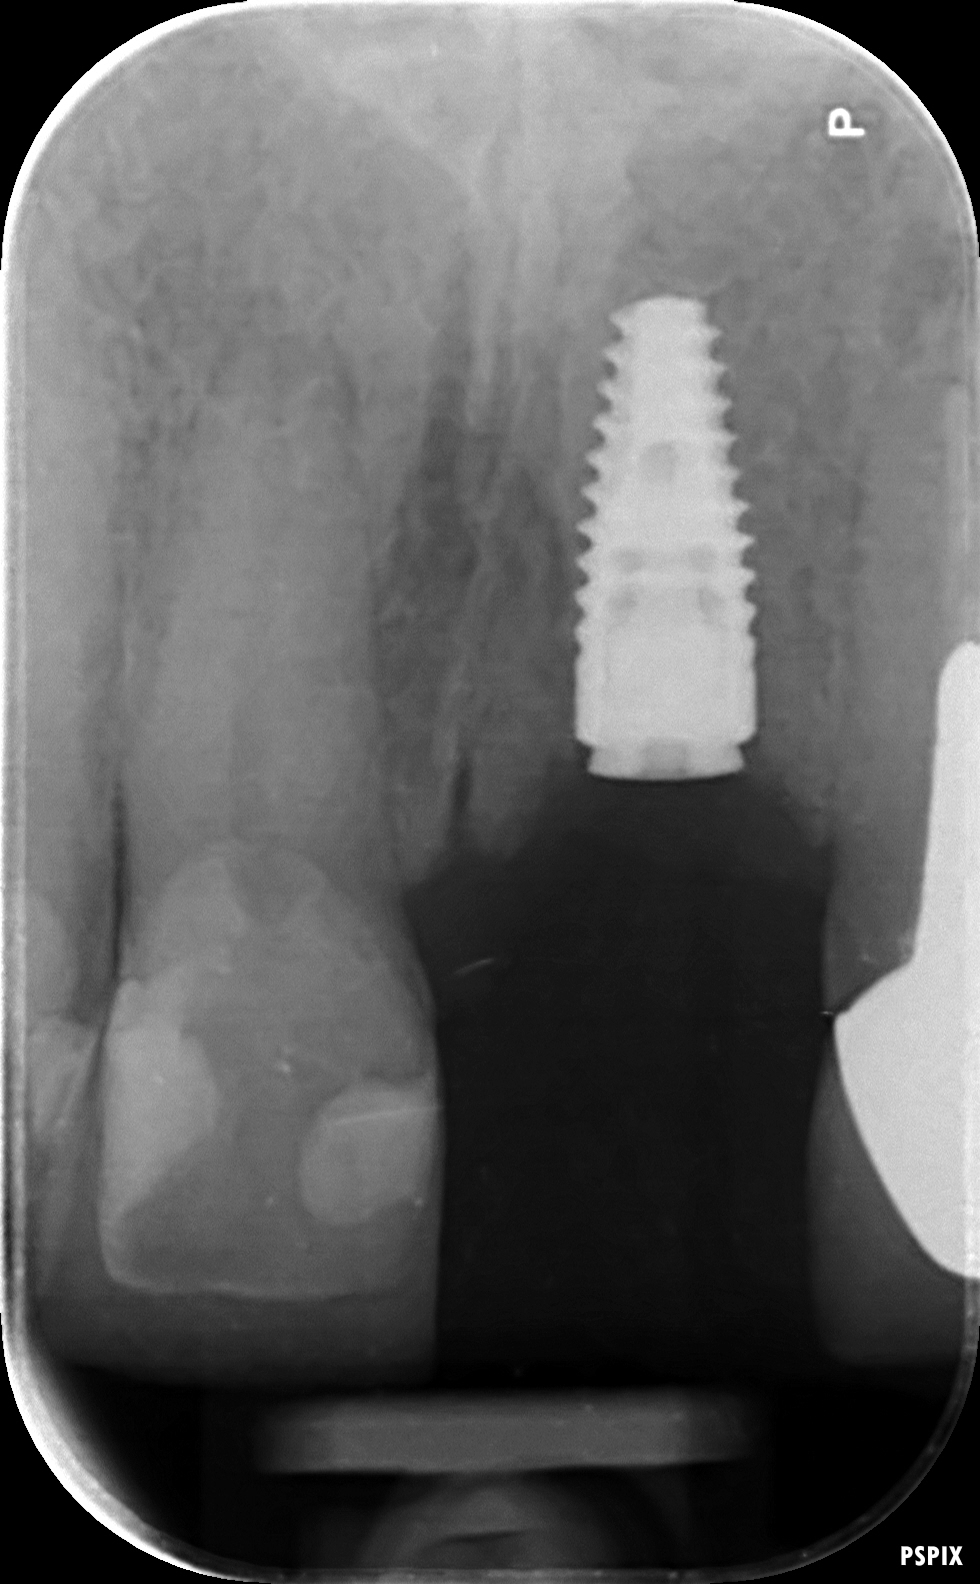

A dental implant is made from titanium and resembles a small screw. Once placed, the surface of the implant interacts with the surrounding bone to form a strong bond and a natural looking artificial tooth (the crown) can then be connected to the implant.

Treatment consists of three phases – planning, surgical, and restorative. The surgical phase consists of a minor procedure to place to implant and often requires the use of a small amount of bone grafting if there is insufficient natural bone. After the implant has integrated with the bone, the new artificial teeth will be designed and constructed to fit over the implants.